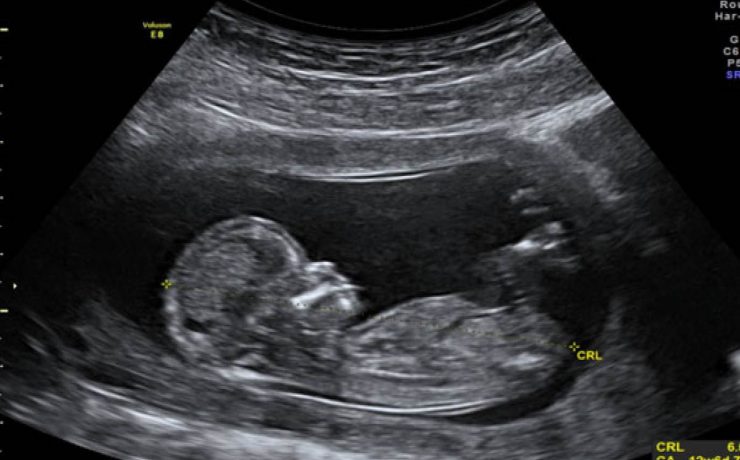

El presente artículo tuvo el objetivo principal analizar la funcion sexual en mujeres portadoras de miomas durante un año, tomando en cuenta el no deseo sexual, la falta de excitación, la falta de orgasmo, presencia de dispareunia y dolor pélvico. El mioma es el tumor solido más frecuente en la